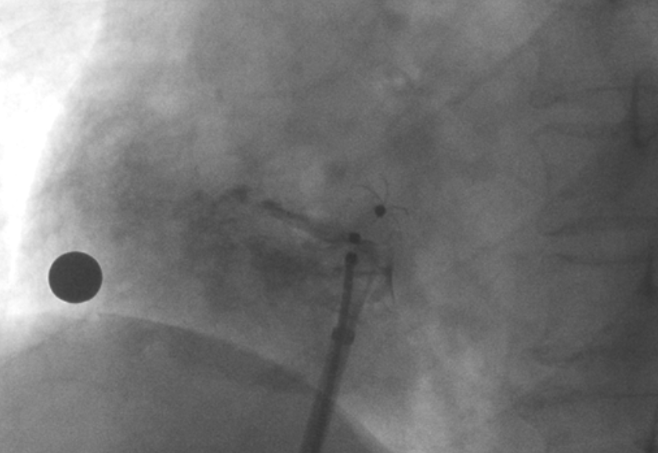

術(shù)中造影顯示患者為PFO且長隧道型,目前市場上已商業(yè)化的PFO封堵器難以滿足該患者解剖結(jié)構(gòu)封堵需求。迪創(chuàng)醫(yī)療自主研發(fā)的OmniSeal PFO封堵器自適應性雙盤貼合設(shè)計能廣泛適應不同PFO隧道長度的解剖結(jié)構(gòu)和形態(tài),其雙盤外包覆式阻流和隧道內(nèi)填充阻流相結(jié)合的雙重阻流設(shè)計,可為此患者實現(xiàn)有效封堵。與此同時,OmniSeal首創(chuàng)的完全可穿刺式設(shè)計,也為此患者最大程度地保留了房間隔區(qū)域穿刺通道,以實現(xiàn)全兼容未來可能的左心系統(tǒng)二次介入術(shù)。術(shù)終造影和心臟超聲顯示封堵完全、效果良好。作為OmniSeal的首例臨床應用,本次手術(shù)的順利完成和優(yōu)異效果充分體現(xiàn)了產(chǎn)品的設(shè)計創(chuàng)新優(yōu)勢。

造影顯示PFO封堵完全,無殘余分流, 試驗器械充分舒展并貼合良好